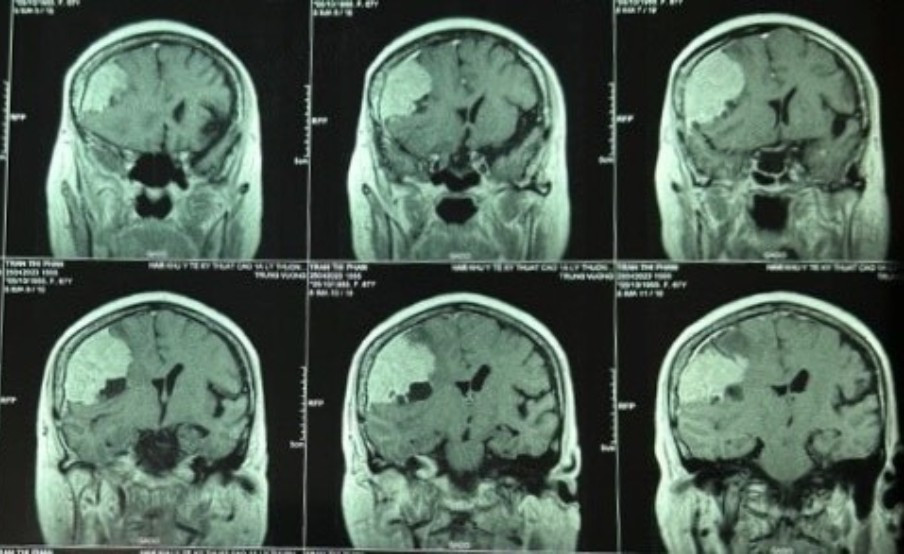

Hình ảnh khối u màng não "khủng" có kích thước to hơn quả trứng vịt. (Ảnh: BVCC)

Lần này đến khám tại Bệnh viện Trưng Vương, bệnh nhân trong tình trạng đau đầu, yếu nửa người bên trái. Kết quả chẩn đoán phát hiện u màng não lớn vùng thái dương bên phải, có nhiều mạch máu nuôi u.

Theo Bệnh viện Trưng Vương, trước khi phẫu thuật, các bác sĩ đánh giá khối u màng não có quá nhiều mạch máu nuôi nên phải hội ý với bác sĩ chuyên khoa can thiệp nội mạch (DSA). Việc tắc mạch nuôi u để hạn chế máu chảy khi phẫu thuật đã được tiến hành.